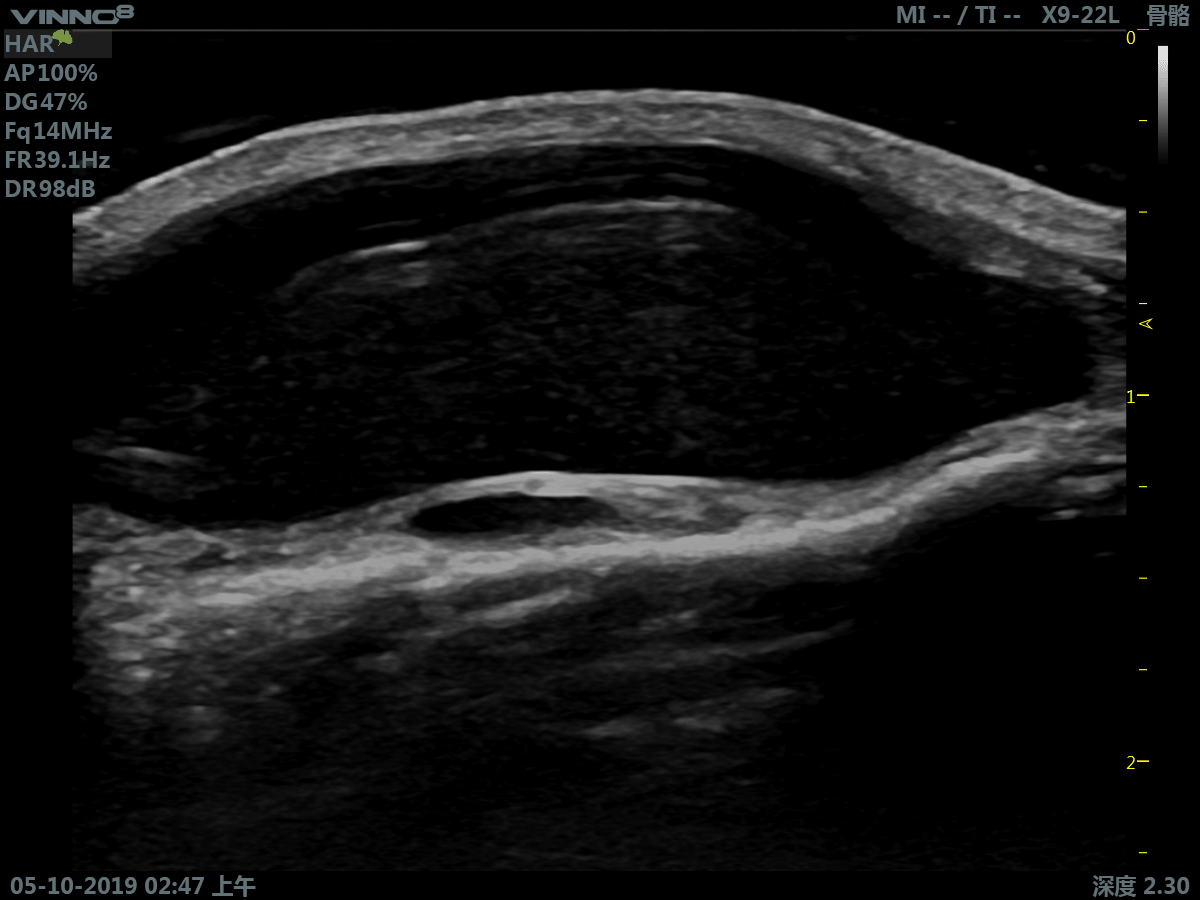

- мелкие объекты (включая щитовидную железу, молочную железу, семенники и т.д.)

- Мускуло-скелетные исследования

- сверхвысокая частота (до 23 МГц на линейном датчике)